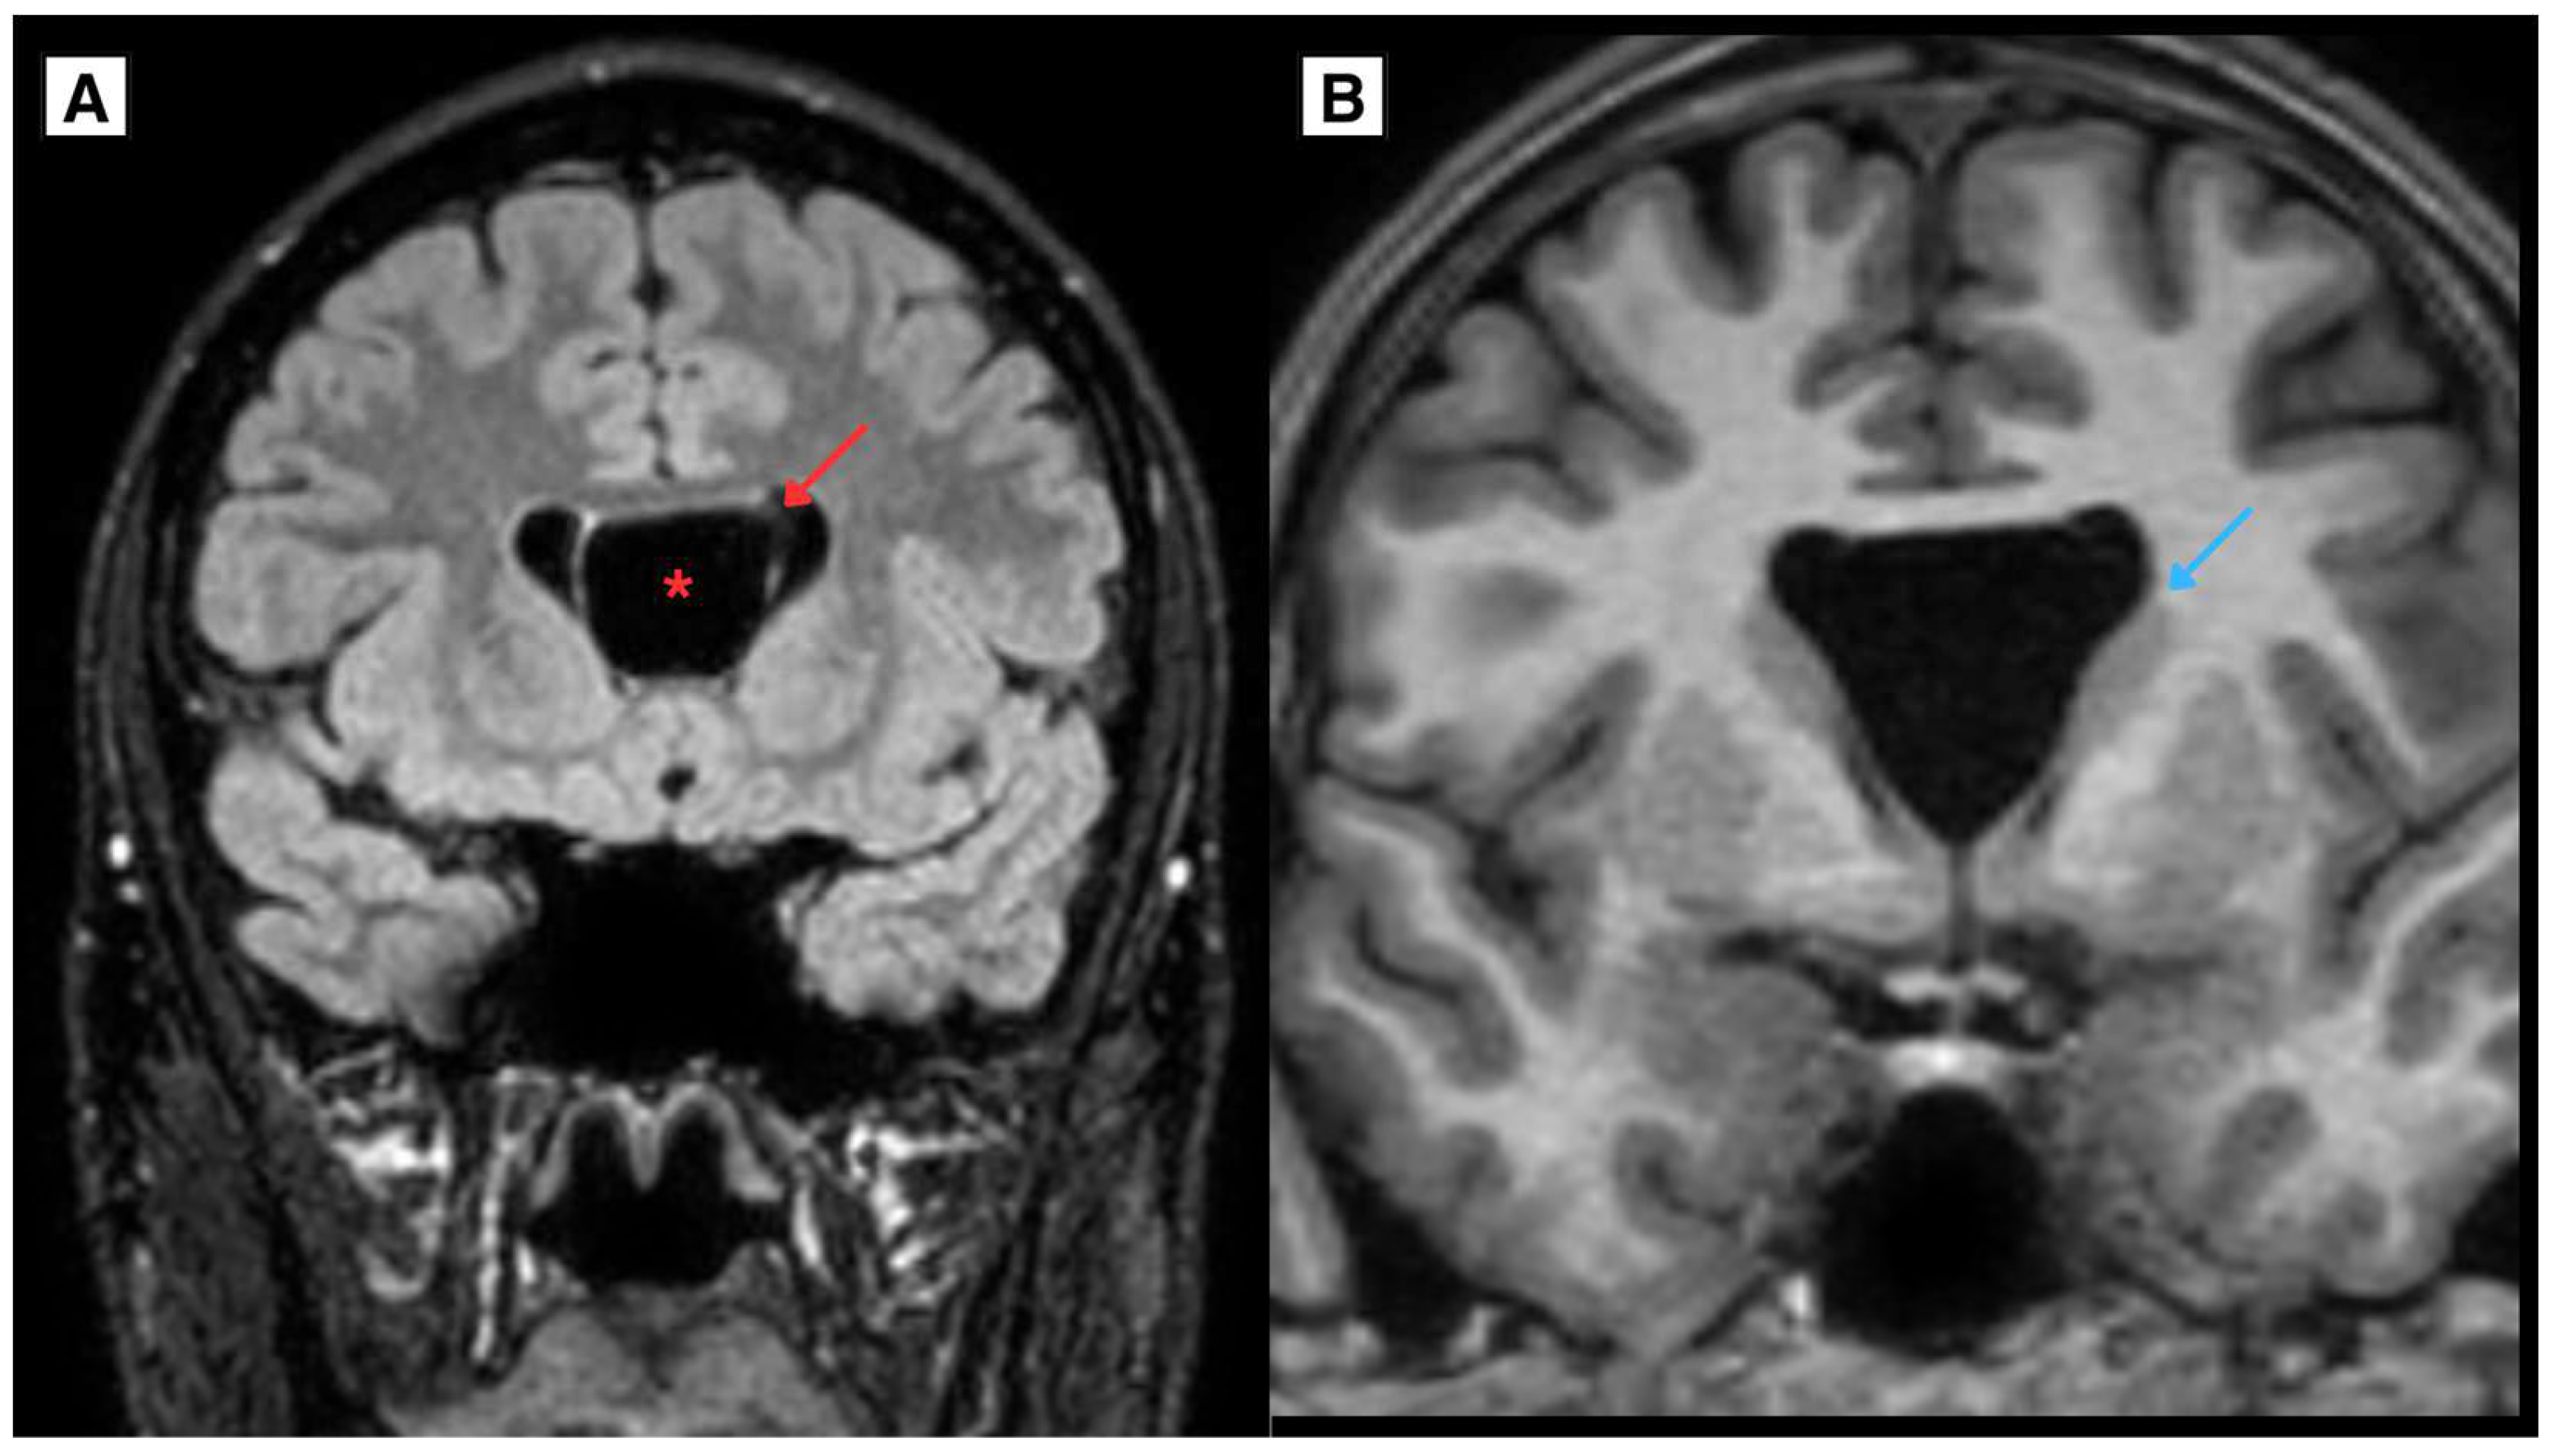

2.2. A Novel Anatomical Pattern in CSP Cyst Imaging